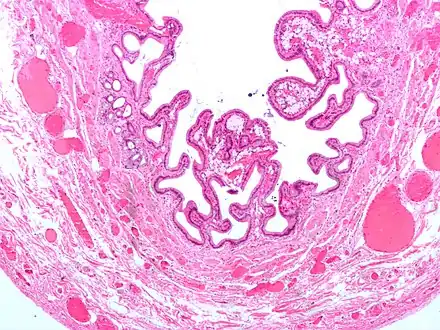

Micrograph of cholesterolosis of the gallbladder